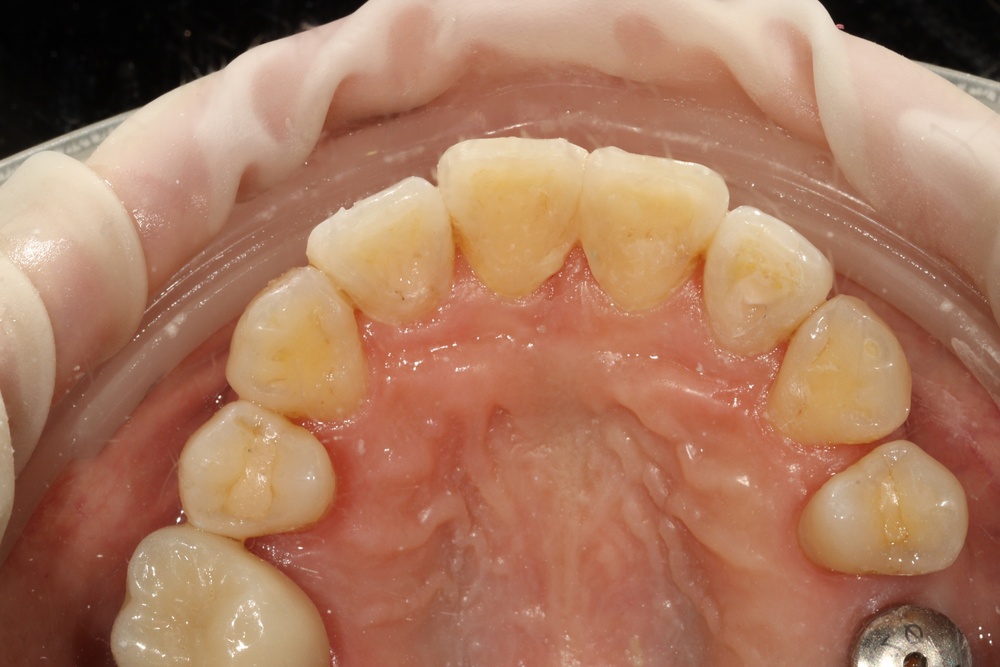

앞니가 비뚤게 나서 교정하러 온 친구입니다.

입천장의 고정식 확장장치를 이용해 좌우로 벌려서 치아를 배열할 공간을 만들었습니다.

그런데 친구가 학교에서 부딪혀서 다쳐 왔습니다.

바로 처치(치아를 철사로 부목 고정)후 신경치료를 진행하였습니다.

이후 치아배열을 마무리하여 가지런한 이를 가지게 되었습니다.